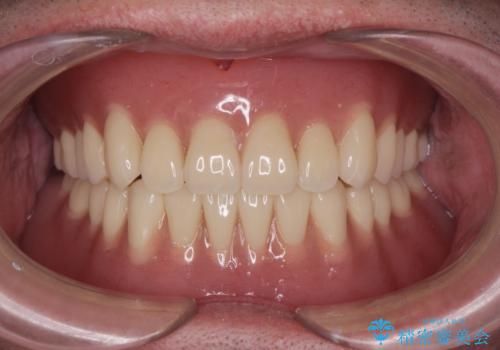

入れ歯掲載症例数57件